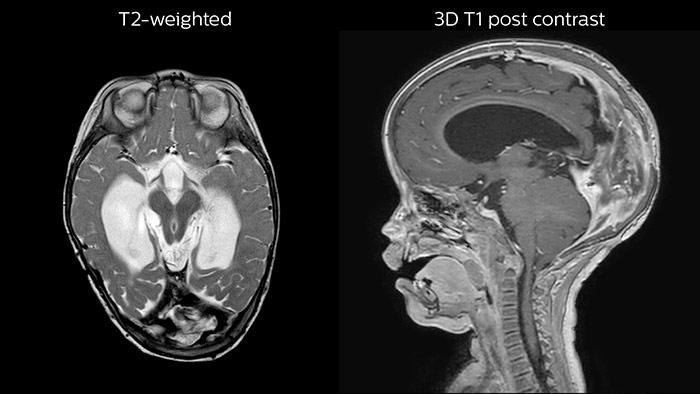

Leukodystrophy in a teenager

Rostral meningitis and arachnoiditis Both images are from the same 3D T1-weighted post contrast sequence in a newborn, under treatment.